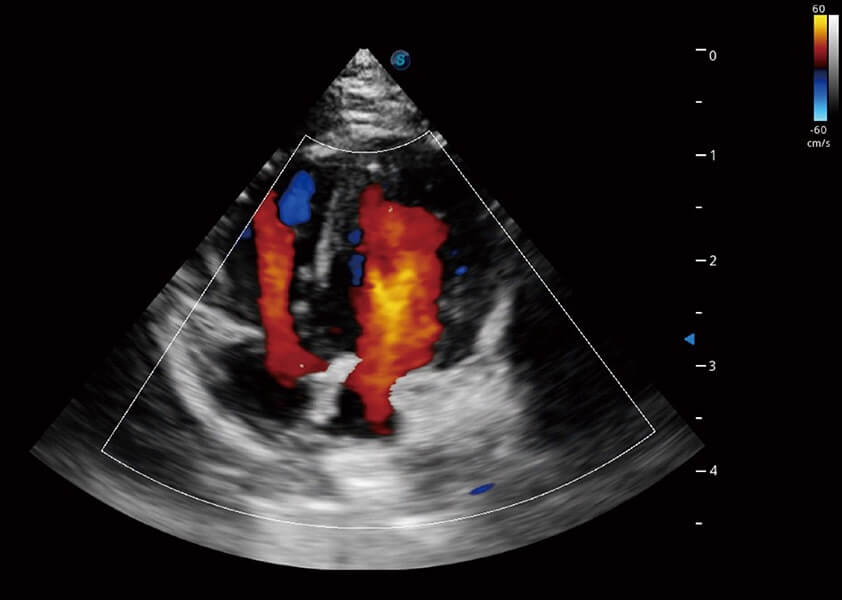

ProPet 60 作为一款高端台式动物超声设备,为动物医生的日常诊断提供了一系列贴合动物临床需求、解决临床实际问题的高级成像功能。凭借全系列高清探头,满足医生对腹部、心脏、生殖、浅表、肌骨等成像的所有需求,切实帮助您提升检查效率,提高诊断信心。

动物是人类最亲密的朋友和最值得信赖的伙伴。1xBET也一直致力于探索动物专用的超声影像解决方案。 全新推出的ProPet系列,是1xBET在动物超声影像智能化、专业化、精准化的一次跨越式革新。动物不能用言语来表述自己的不适,通过超声影像,ProPet系列搭建了动物医生与不同物种沟通的“桥梁”,为动物医生注入了“治愈之力”。